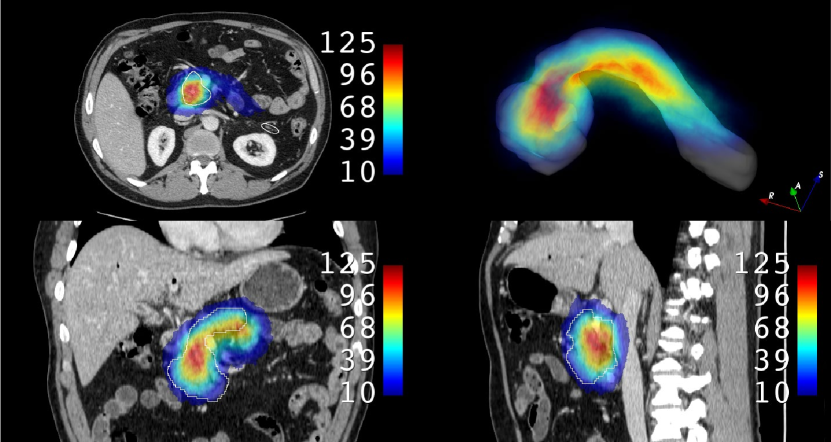

In order to provide an example of the variability of the pancreas parenchyma in terms of size and location, a registration was performed on 281 CTs of the MSD dataset using Elastix software (Klein et al., 2010), adapting inter-subject registration parameters from the study by Qiao et al. (2016) to the CT domain. Subject 29 of MSD was considered a reference image by virtue of its high-quality image and centrality within the range of variations observed in the dataset. A Hounsfield unit (HU) from 100 to 500 was used for all the images to improve the registration process, enhancing bones and brighter abdominal structures. The results are illustrated in Fig. 10. A histogram with the frequency distribution is shown in Fig. 11. It was created by measuring the volumetric distances from the centroid of the pancreas in subject 29 of MSD to the centroids of the pancreas from all other subjects after performing the registration.